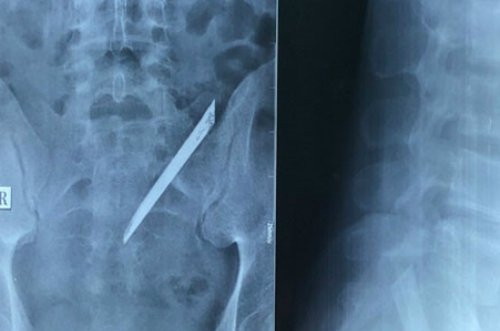

Cách đây 4 năm, chàng trai bị đâm vào vùng hông lưng. Bác sĩ không phát hiện dị vật, đã sơ cứu, may vết thương. Gần đây anh đau lưng nên đi khám.

Lưỡi dao nằm trong cơ thể bệnh nhân. (Ảnh bệnh viện cung cấp)

Tiến sĩ Nguyễn Đình Phú, Phó Giám đốc Bệnh viện Nhân dân 115 cho biết các bác sĩ đã phát hiện dị vật trên lưng bệnh nhân. Ngày 15/12 kíp phẫu thuật đã lấy ra lưỡi dao dài khoảng 12 cm khỏi cơ thể bệnh nhân. Hiện bệnh nhân đã ổn định sức khỏe.

May mắn lưỡi dao nằm nhiều năm trên lưng bệnh nhân nhưng không chạm vào rễ thần kinh và chùm đuôi ngựa. Dị vật chỉ chạm vào cột sống vùng xương cùng cụt, gây tổn thương bao cơ vùng cạnh cột sống nên bệnh nhân chỉ đau nhức lưng khi vận động. Thông thường dị vật để lâu trong cơ thể có thể gây nhiễm trùng nguy hiểm tính mạng nhưng trường hợp này không hề viêm nhiễm.